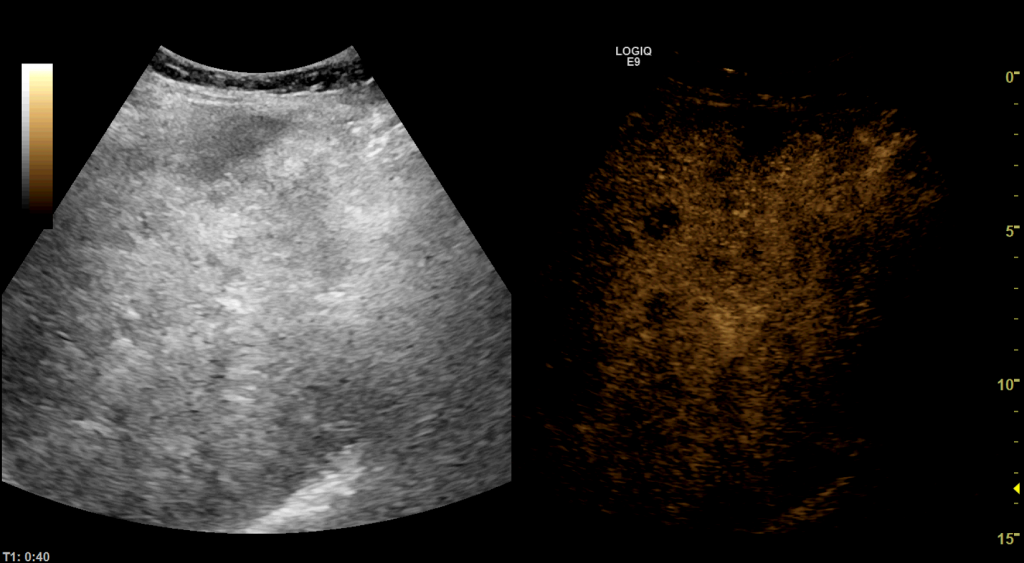

Eine weitere Option ist die kontrastverstärkte Ultraschalldiagnostik, bei der ein Ultraschallkontrastmittel gespritzt wird, wodurch sich z.B. Tumore in der Leber sehr genau differenzieren lassen. Durch dieses schonende Verfahren lassen sich erweiterte bildmorphologische Abklärungen ohne Einsatz nebenwirkungsreicher Medikamente oder Röntgenstrahlen durchführen.

Im Falle von Leberherden lassen sich diese wiederum bei Verdacht auf eine mögliche bösartige Läsion im Kontrastmittelultraschall direkt punktieren, um eine winzige Gewebeprobe für genauere Untersuchungen zu gewinnen. Im Falle nachgewiesener bösartiger Leberherde können diese wiederum in Kooperation mit der 2. Med. Klinik der Universitätsmedizin Mannheim auch über eine Ultraschallgesteuerte Mikrowellenablation direkt koaguliert und behandelt werden.